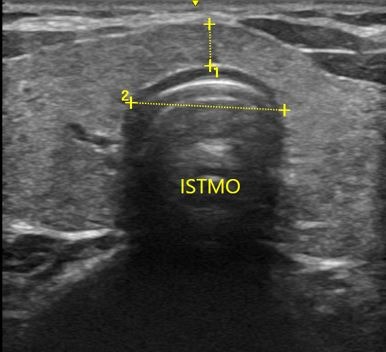

Tireoide

USG, TC e RN de tireoide

Vamos esclarecer as principais dúvidas de como tratar os portadores de hipotireoidismo, hipertireoidismo, nódulo de tireoide, câncer de tireoide. Além disso um treinamento sobre ultrassonografia de tireoide, PAAF e alcoolização percutânea de nódulos (IPE). Ao final, estar apto a decidir quando usar medicações, operar ou usar radioiodoterapia.